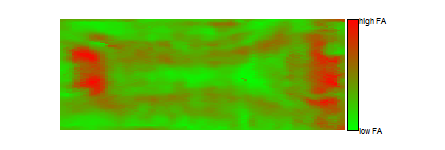

4.2 Flattened FA Representation

A primary goal from the principal surface fitting is to flatten the surface and to make a 2D FA image. That is, our goal is to use DTI-based morphometric information to create 2D images of MR contrast properties, such as FA maps. First, we project each data point onto the surface by a grid search method. Then we smooth the associated FA value on the surface by calculating a local average. Interpolating this smooth onto a grid yields a 100×100100100100\times 100 2D FA image displayed in the right panels of Figure 5. That is, right panels represent the flattened surfaces of the corresponding left panels. The bottom panel shows the average FA map, which shows an overall visualization of 2D FA maps for all the scans. Another important fact is from left panels in Figure 5 and right panel in Figure 1, we can see that important information of the FA values is retained, which is to say, it may be sufficient to visualize the 2D FA values instead of the original 3D FA values.

Figure 5: In the left column, top four panels illustrates the the original corpus callosum from four different scans with their fitted principal surfaces. The scattered points are the original data points and the surface across the middle of them is the fitted principal surface. The bottom panel shows the average fitted principal surface for all the 466 scans. Red color suggests higher FA value while green means lower one. The right panels are the corresponding flattened surfaces. In the 2-D image, red color represents higher FA while green suggests lower one.